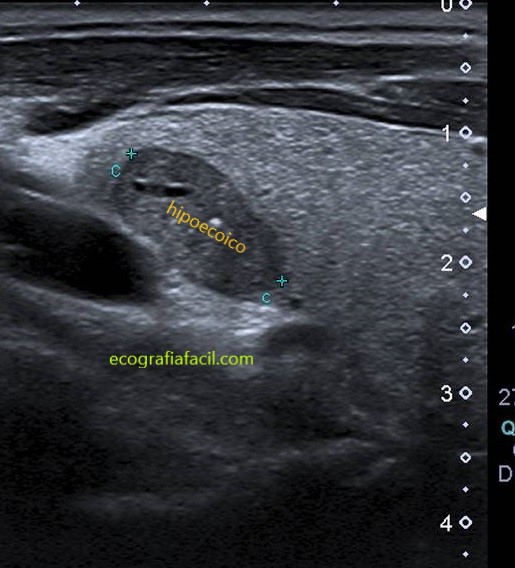

HIPOECOICO:

HIPOECOICO+: